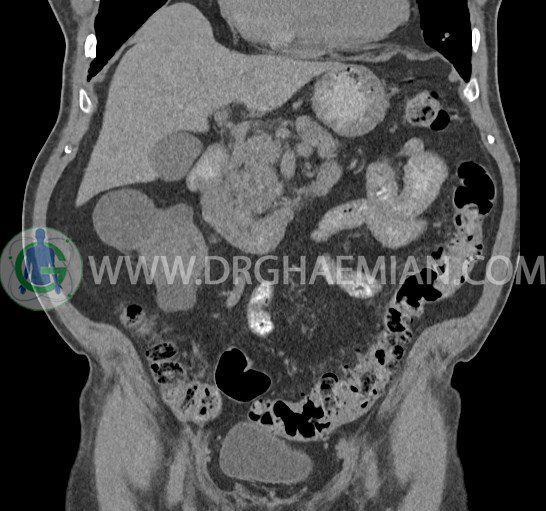

سی تی اسکن لگن یکی از روش های تصویربرداری با سی تی اسکن است. این روش با استفاده از تشعشعات تصاویر عرضی از ناحیه شکمی ایجاد میکند. در این کیس ديورتيكولوزيس، کیست های کورتیکال در هر دو کلیه، لنفادنوپاتی، کلسیفیکاسیون دیواره آئورت و شریان ایلیاک، تغییرات DJD ناحیه توراکولومبار و پروستات بزرگتر از عادی دیده می شود.

در سي تي اسکن اسپيرال شکم و لگن با و بدون کنتراست خوراکی و وريدی (مولتي ديدکتور 16 با مقاطع ظريف و بازسازي هاي ساژيتال و کرونال):

– کيست هاي کورتيکال ساده به قطر 5 mm تا 50 mm در کليه راست و به قطر 5mm تا 55 mm در کليه چپ

– توده ايزودنس به ابعاد mm 17 x 28 در پره ائورت مجاور قسمت تحتاني D3 دئودنوم مطرح کننده لنفادنوپاتي و با احتمال کمتر آنوريسم ترومبوزه (نيازمند مطابقت سونولوژيک)

– ديورتيكولوزيس در کولون نزولي وسيگموئيد

– تغييرات DJD در ناحيه توراکولومبار و

– پروستات به ابعاد mm 45 x 54، بزرگ تر از نرمال

مشهود است.